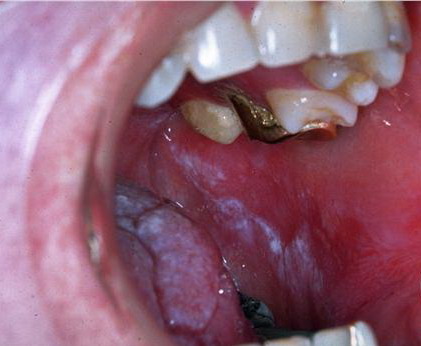

circinate erosive balanitis=التهاب الحشفة المتحلق السحجي circinate erosive balanitis Balanitis, circinate: A form of skin inflammation around the penis in males with Reiter’s syndrome. The skin around the shaft and tip (glans) penis can become inflamed and scale. This inflammation around the penis can be helped by cortisone creams (such as TOPICORT). Reiter’s syndrome […]